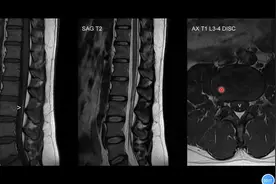

腰椎磁共振报告经常说“椎体脂肪沉积”,到底是个什么鬼,严重吗

腰椎椎体脂肪沉积

腰椎MRI病例分享:终丝脂肪沉积如何诊断?专科医生讲解#健康科普